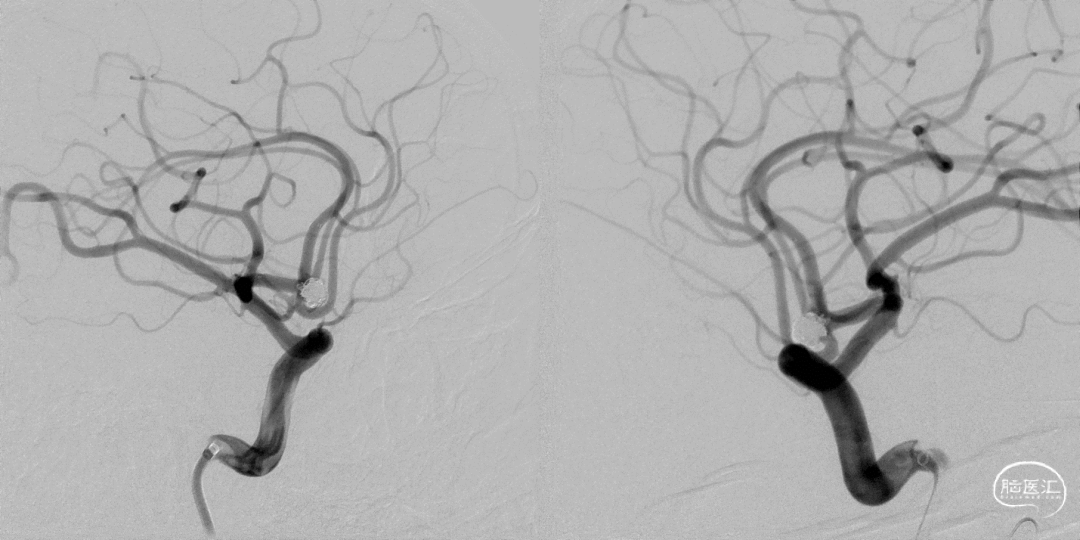

DSA提示左侧前交通动脉瘤大小4.5×4.7mm,宽颈3.4mm,瘤顶有一子囊。

术后正侧位片 动脉瘤完全不显影,双侧A2显影均良好;术后下撤Heralder®DA远端通路导引导管再行颈内动脉造影显示颈内动脉全程无痉挛,提示Heralder®DA远端通路导引导管对颈内动脉的刺激小,无损伤。